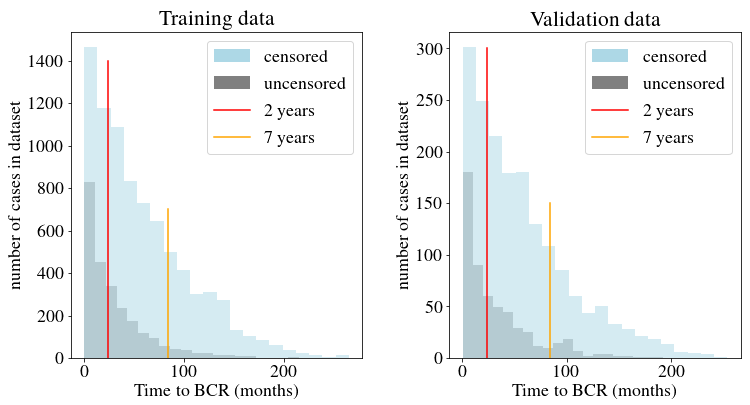

Images from all but one TMA are shuffled and split into training, validation and test sets, stratified by prostate Gleason annotation. One TMA is left out as a separate test set to evaluate model performance on a set with a unique staining bias. \tablereftab:dataset summarizes the number of images per dataset split. The distribution of event times for censored and uncensored patients in the training and validation datasets is shown in \figurereffig:apd_data_distribution.

In total, our survival dataset contains 17,230 images with prostate tissue, of which 60 images that either contain little to no tissue or are of poor quality (e.g. artifacts in the image) are omitted. Additionally, 3,624 patients with unknown relapse time or censoring status are excluded. 709 patients fall under the filtering criterion described in \sectionrefsec:dataset. Since multiple exclusion criteria may apply to one patient, 14,479 patients remain in the final survival dataset. The dataset distribution is shown in \figurereffig:apd_data_distribution for the training and validation sets. 90% of uncensored events occur prior to 7 years, 44% prior to 2 years.